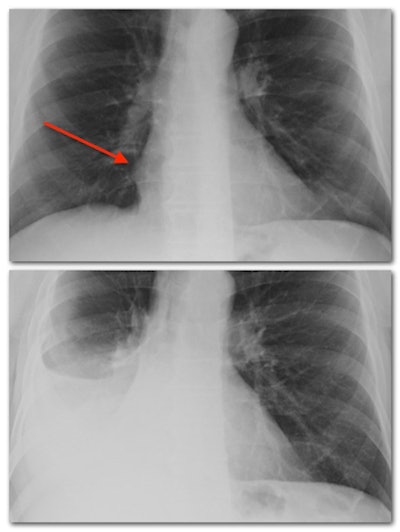

- Atelectasis: I would guess atelectasis is the least familiar word on this list due to its lack of use outside of medicine. Atelectasis (from the Greek atelēs ektasis, literally "imperfect extension") simply means collapse. Collapse of the lung occurs under two general conditions: when it is compressed from the outside or when the airway supplying the lung (or part of the lung) is obstructed. Major causes of compression are pleural effusion and pneumothorax. Obstruction can be caused by many conditions, the most serious being lung cancer. Occasionally the entire lung can collapse, but more commonly only part of the lung is involved. Many times partial atelectasis creates flat, thin areas of collapsed lung that radiologists describe as plate-like or band-like (we are sometimes not the most creative in our naming). Depending on its size and configuration, atelectasis can look more similar to either consolidation or scar.

- Pleural effusion: All right, one last visit to our lung anatomy textbook for this term and the next. A pleural effusion means fluid accumulation in the pleural cavity, a potential space that is located between the lungs and the rib cage. "Potential space" is not a new home flipping show; it means a space that is normally empty but has the potential (aah, get it?) to be filled with something, like the inside of an uninflated balloon. The pleural cavity is sandwiched between two thin membranes called the pleura, one of which covers the outside of the lungs and the other the inside of the rib cage. Normally the pleural cavity contains a minuscule amount of fluid for lubrication purposes, but under certain conditions it can fill with fluid and create a pleural effusion. If it is large enough, one can see a horizontal line representing the top of the fluid collection with slight sloping up on each side, a characteristic shape called a meniscus. Pleural effusion is a common cause of atelectasis in the adjacent lung. Many different types of conditions can cause pleural effusions, with heart failure and pneumonia among the more common ones. (A chest x-ray example of pleural effusion can be seen above under "silhouette sign").